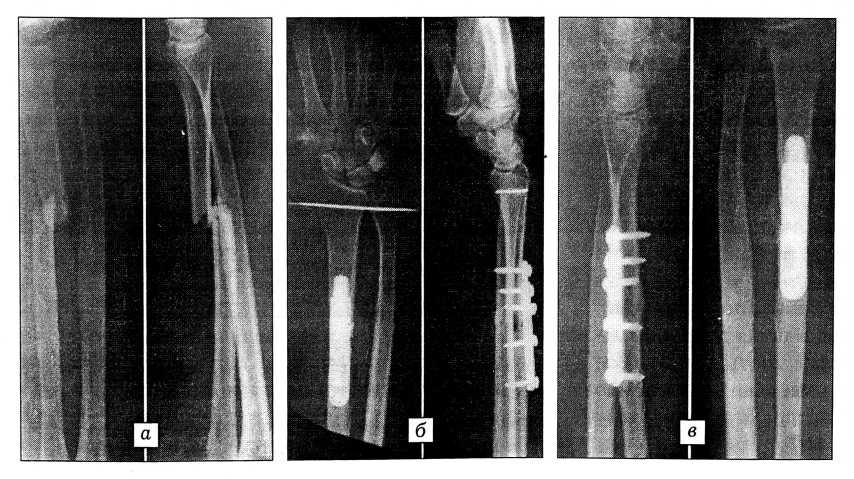

Данный вид остеосинтеза удобен тем, что позволяет осуществлять репозицию отломков при различных вариантах их смещения, в том числе с захождением друг за друга. Пластина дает возможность дистрагировать отломки, сопоставлять их и компрессировать с последующим динамическим обездвижением сегмента до полного заживления перелома (рис. 2).

Рис. 2. Рентгенограммы больного с косопоперечным переломом лучевой и вывихом головки локтевой кости. а — до операции; б — после накостного компрессионно-динамического остеосинтеза и вправления головки локтевой кости; в — через 8 мес после операции: первичное сращение перелома.